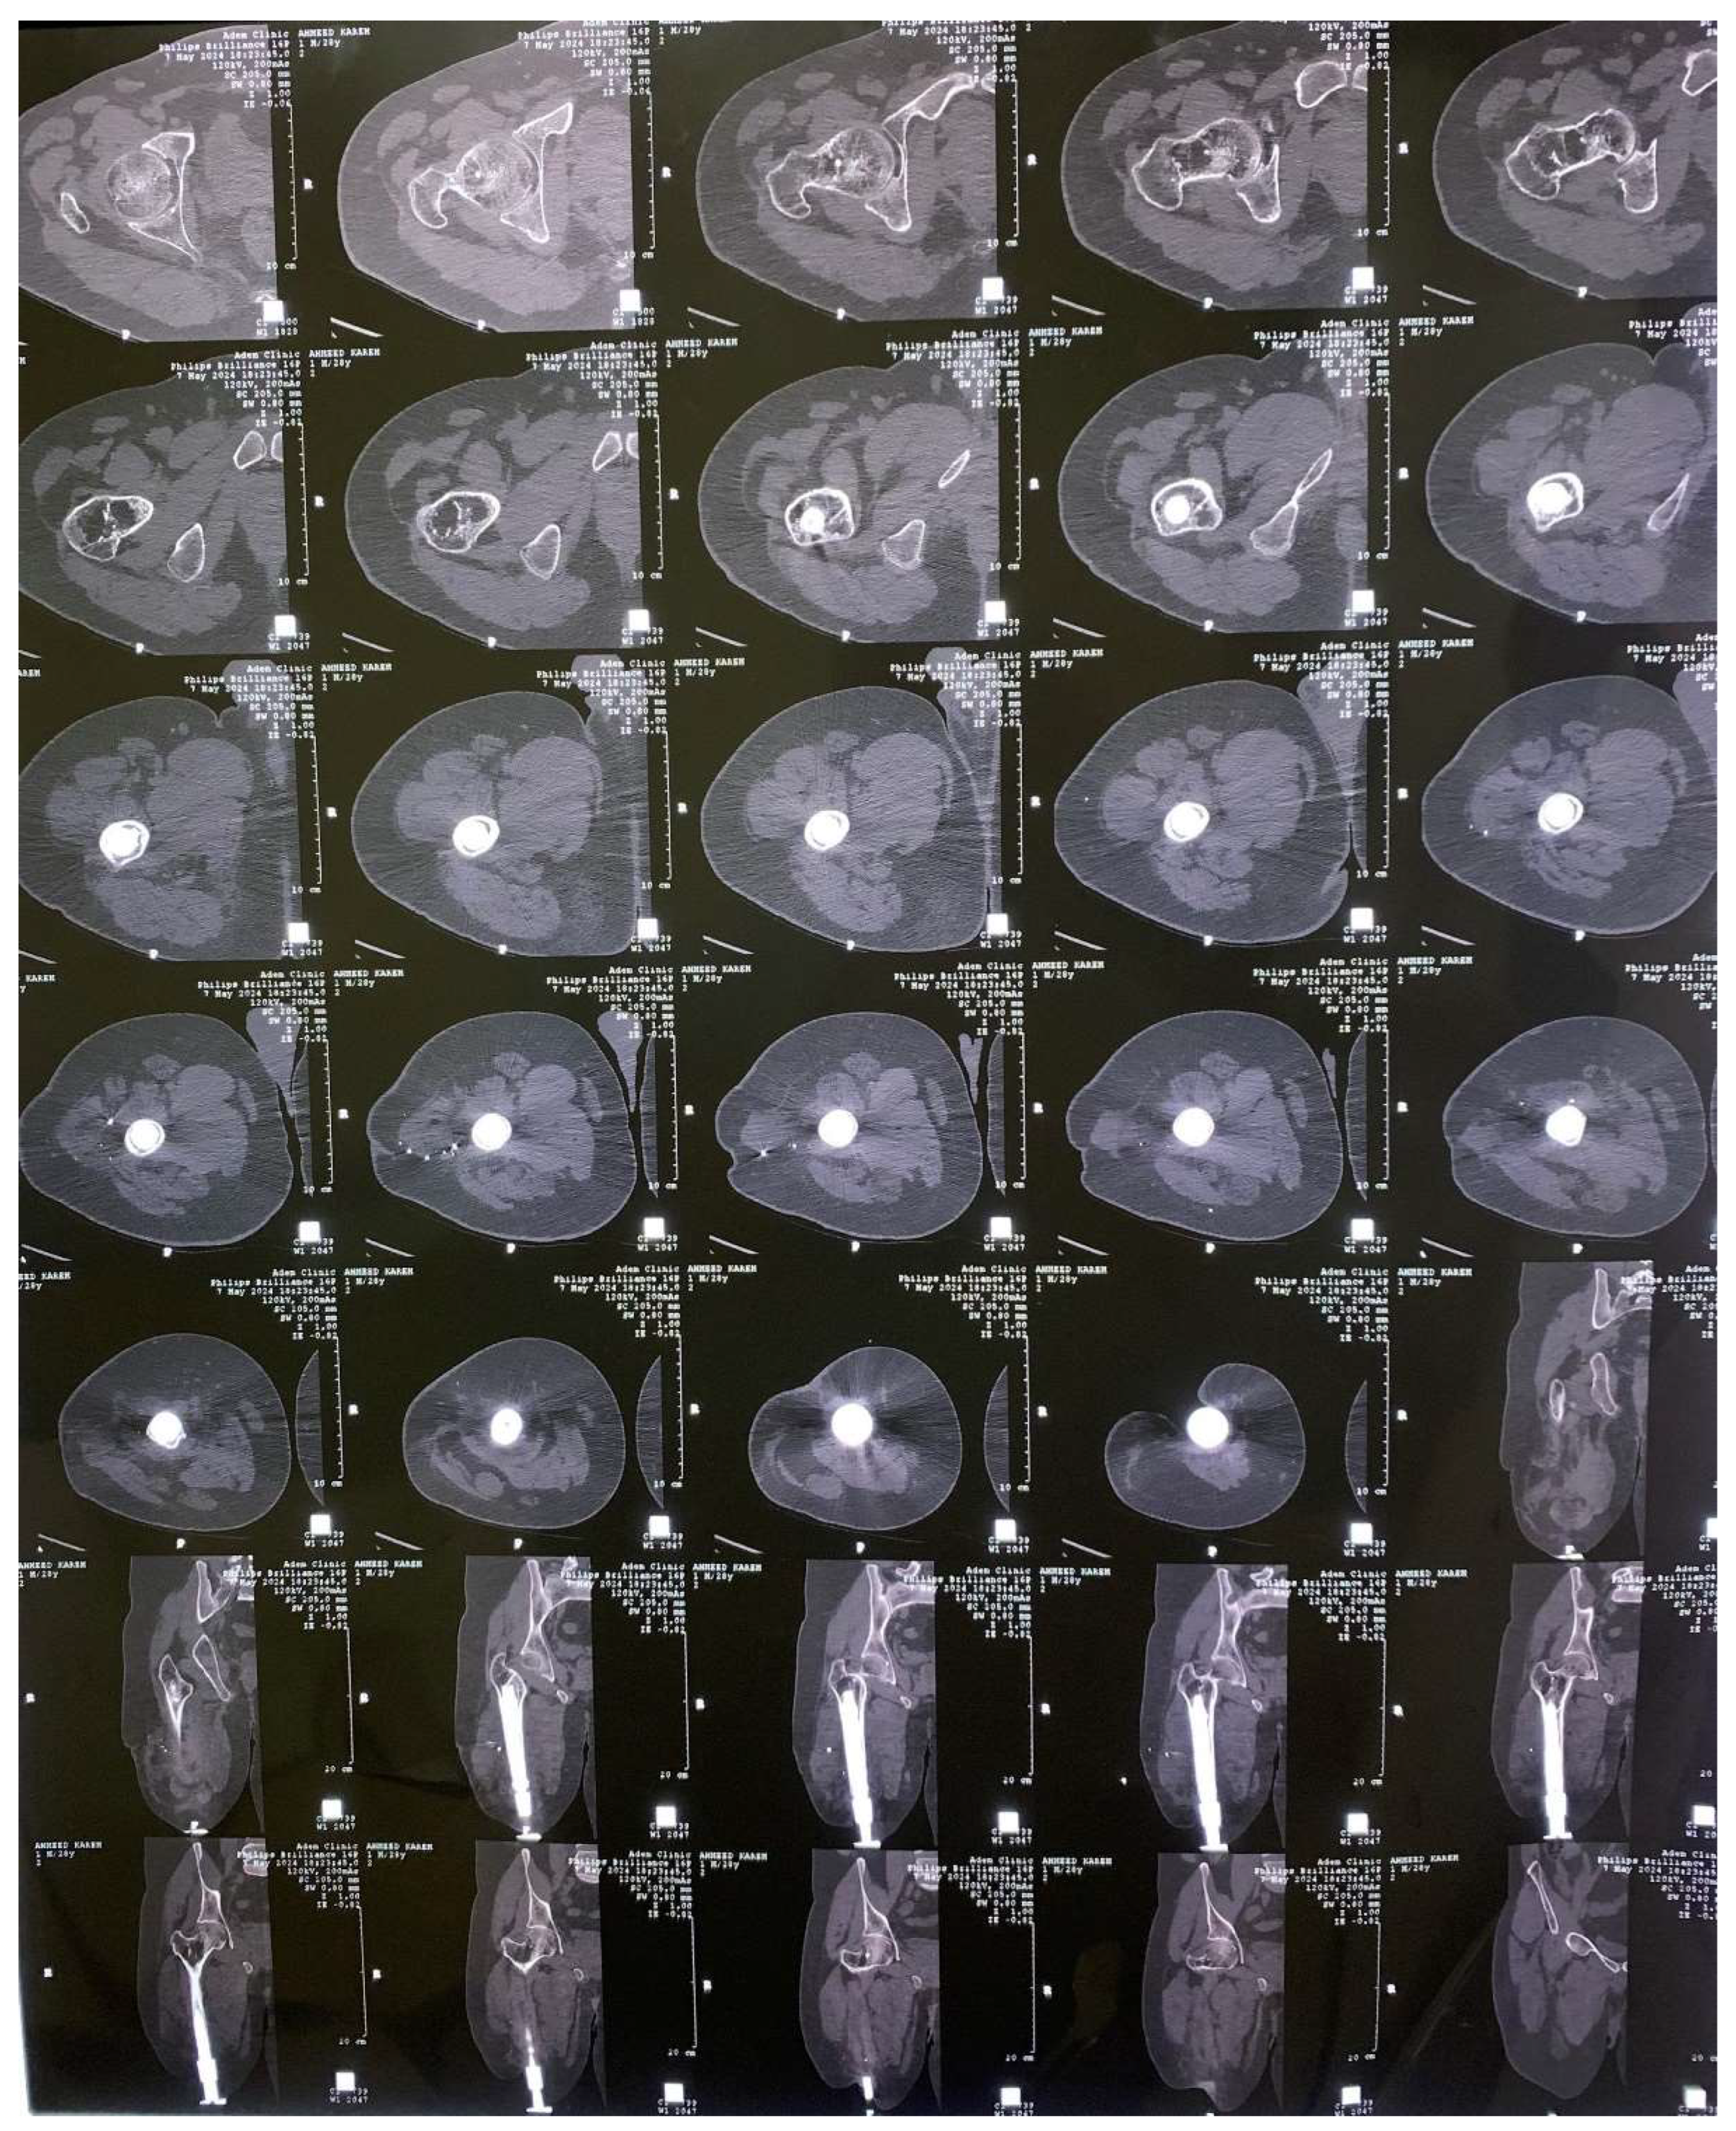

2. Experimental Works

3.1. CAD Model